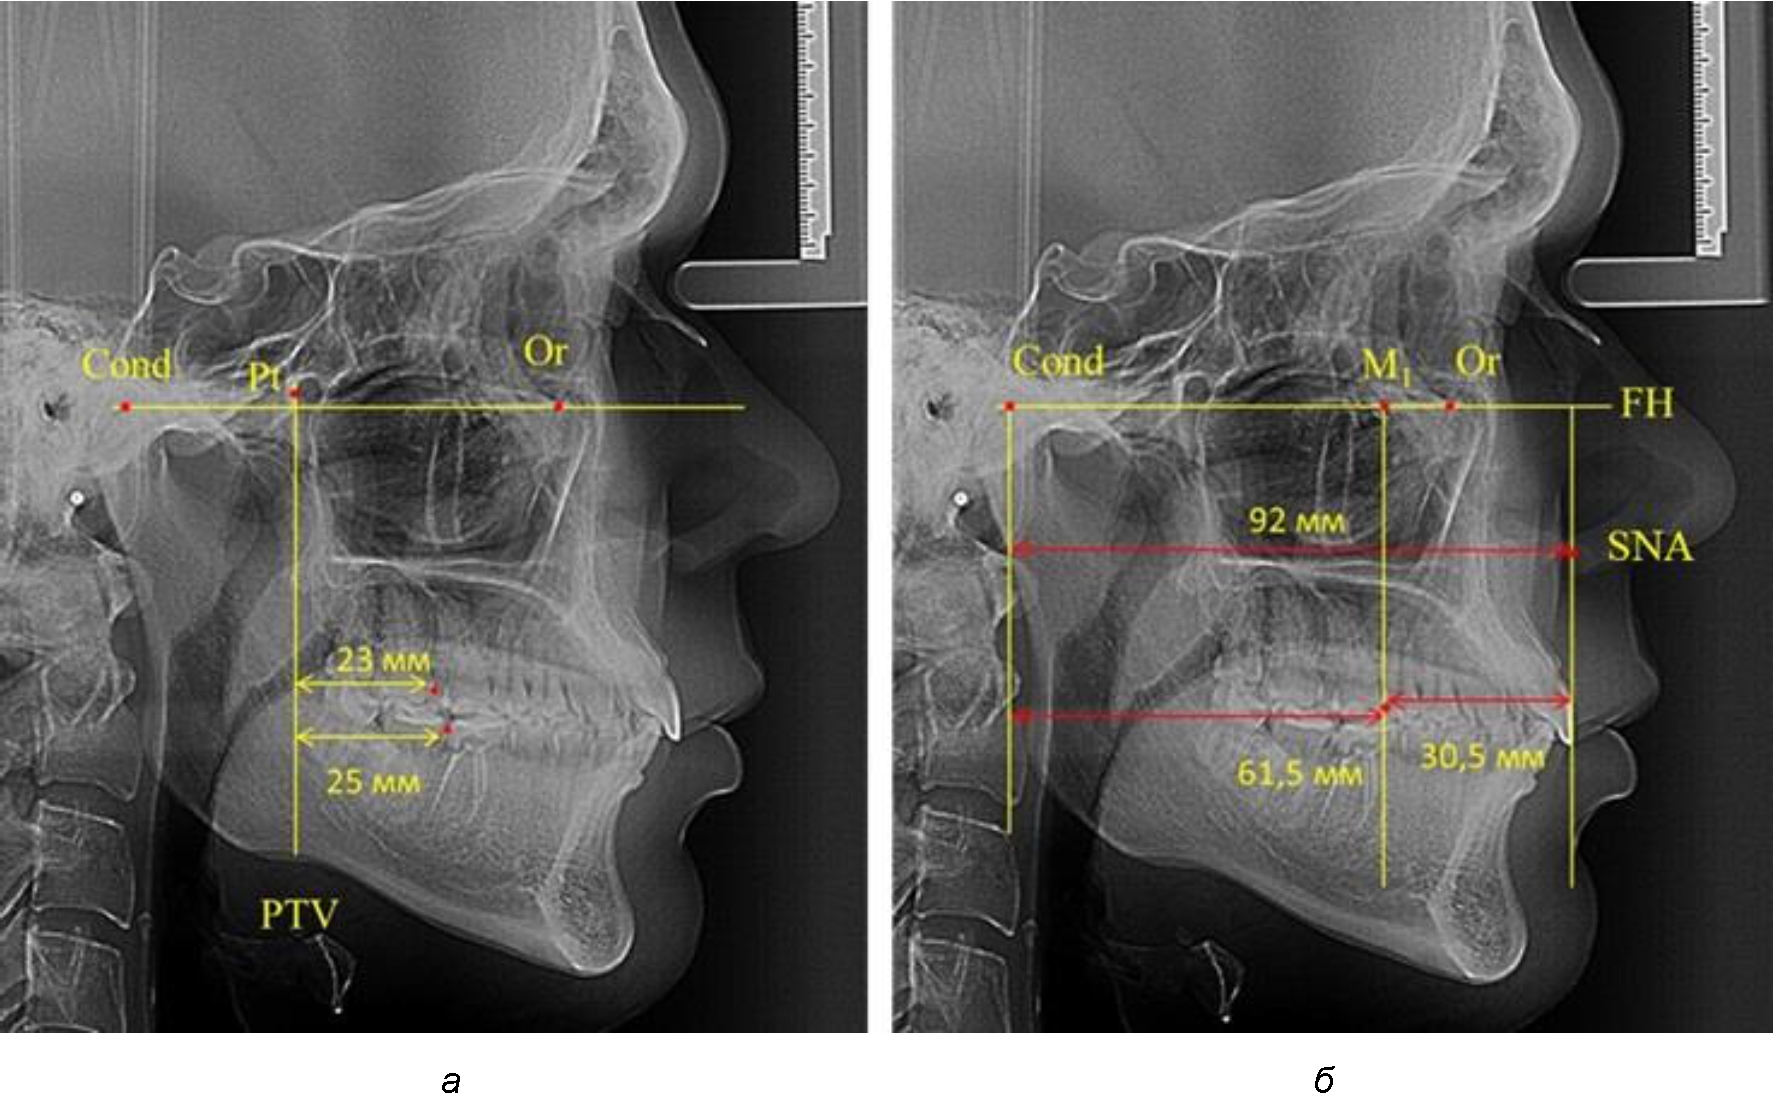

Рис. 1. Метод определения положения первых верхних моляров по Ralph E. McDonald (а) и по предложенному методу (б)

Согласно указанному методу на рентгенограммах проводили Франкфуртскую горизонталь. Учитывая мнения специалистов относительно ориентиров для построения и вариабельность положения наружного слухового прохода, в качестве задней точки использовали верхнюю выпуклость суставной головки нижней челюсти («Cond»). Передняя точка традиционно располагалась на нижнем крае глазницы и определялась как орбитальная точка Or.

Находили положение точки Pt, которая располагалась на пересечении нижнего края круглого отверстия и задней стенки крыловидно-верхнечелюстной щели, и перпендикулярно к Франкфуртской горизонтали проводили крыловидную вертикальную линию, которую принято обозначать как плоскость PTV. Расстояние от крыловидной вертикальной плоскости PTV до дистальной поверхности верхнего первого постоянного моляра определяло его положение, которое, по мнению R. E. McDonald, соответствовало возрасту пациента, увеличенному на 3 мм.

При проведении анализа к Франкфуртской горизонтали проводили передний и задний перпендикуляры. Передний спинальный перпендикуляр проходил через выступающую точку передней носовой ости (spina nasalis anterior – SNA), а задний суставной перпендикуляр опускали из кондилярной точки Cond. Молярный перпендикуляр проводили через медиальную поверхность первого постоянного моляра. Указанная вертикаль отделяла замещающие зубы постоянного прикуса от добавочных зубов (постоянных моляров), что вполне логично для анализа положения первых постоянных моляров в гнатическом комплексе (рис. 1).

Если метод R. E. McDonald позволял оценить только положение первых постоянных верхних моляров, то предложенный метод учитывал сагиттальные индивидуальные размеры гнатического отдела лица и определять соотношение межу его размерами в передней и задней части.